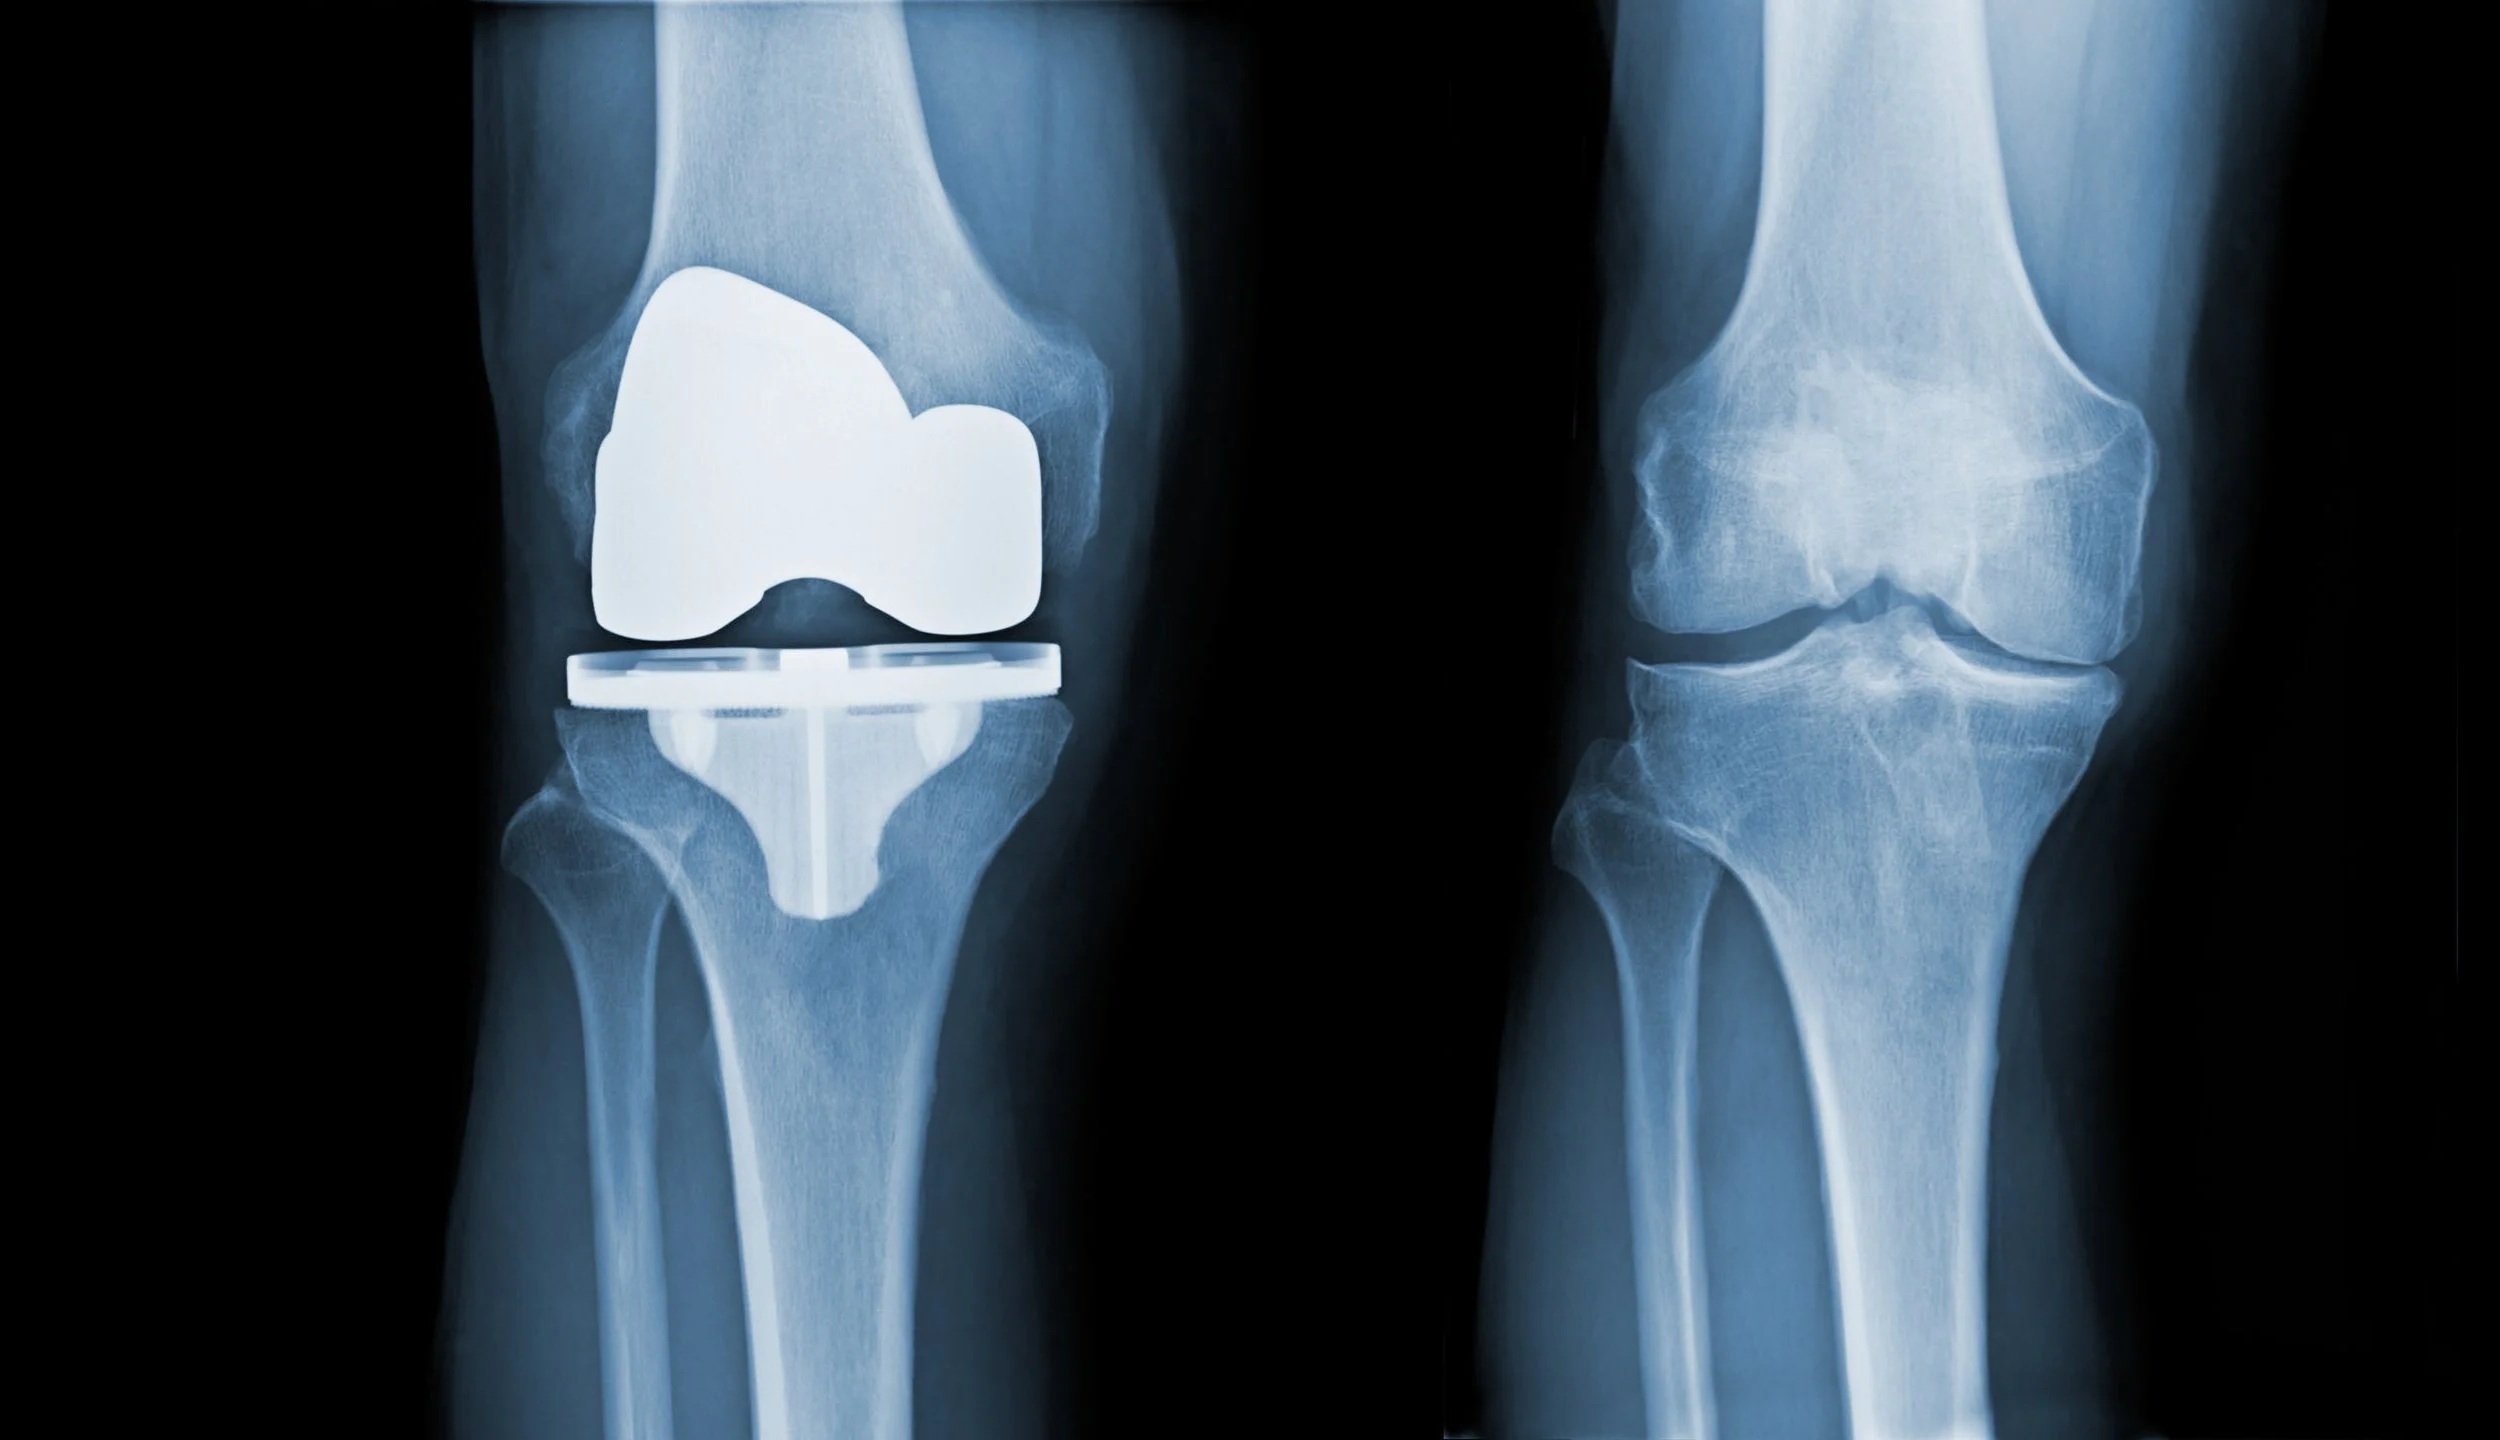

In-depth radiographic analysis of unicompartmental arthroplasty (published in The Knee).

Study of a novel cementing technique in total knee arthroplasty (published in BioMed Research International).